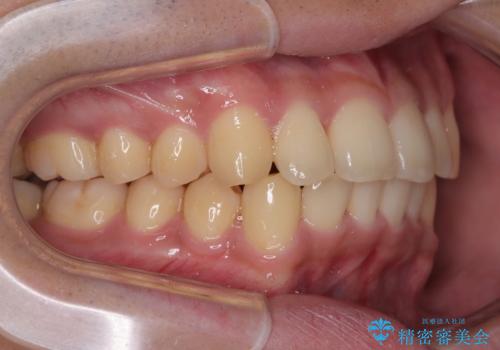

- 上下前歯の捻れやデコボコを気にして来院された患者様です。

マウスピース矯正でもワイヤー矯正でも対応可能でしたが、極力楽をして治したいとのことでワイヤー装置にて治療をおこなうこととしました。

口元はそれほど突出しておらず、患者様自身も気にしていらっしゃいませんでしたが、前歯の捻れやデコボコを解消すると、前方に拡大され、治療後に出っ歯仕上がりとなるリスクがあったため、補助装置により上顎臼歯を後方移動していくこととしました。

昼休みを活用して通院してくださり、1年半であっという間に終えることができました。